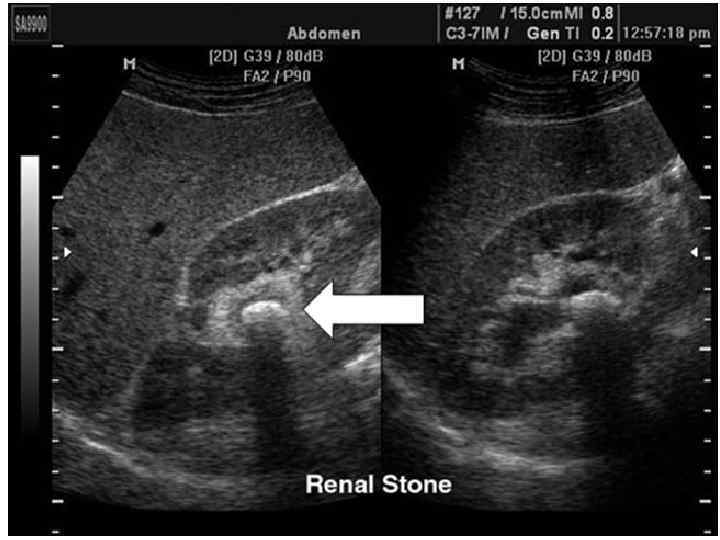

Диагностика • Анализ анамнеза заболевания и жалоб. • Анализ анамнеза жизни. • Данные врачебного осмотра (положительный симптом поколачивания — боль при легких ударах в поясничной области). • Анализ крови — сдвиг лейкоцитарной формулы влево, повышение СОЭ (скорость оседания эритроцитов, неспецифический признак воспаления). • Анализ мочи — появляются эритроциты, единичные цилиндры (своего рода слепки канальцев почек, которые состоят из свернувшихся в кислой среде мочи белков и других компонентов, важный признак почечной патологии) и соли, лейкоцитурия (обнаружение лейкоцитов в моче — признак воспаления) Эндоскопические методы: • Цистоскопия • УЗИ Рентгенологические методы: • обзорная рентгенография брюшной полости • экскреторная урография • Динамическая сцинтиграфия • Компьютерная томография с контрастированием

УЗИ